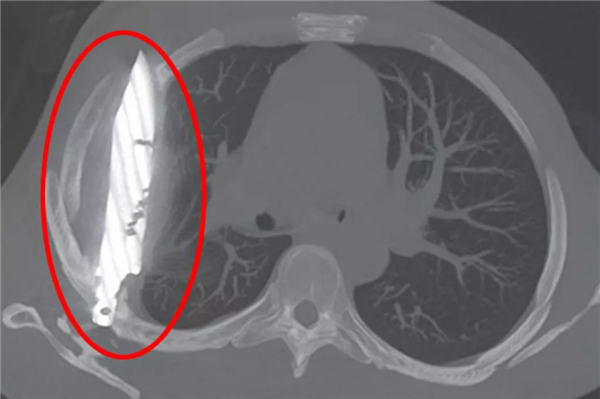

前段时间,《国家医学图书馆》发表了一个惊悚的案例,非洲坦桑尼亚一名44岁男子因为右胸疼痛流脓去医院看病,结果发现在他体内“藏着”一把刀。

就这样,这把刀从右肩胛骨刺入,完美避开体内重要的器官,然后一直隐藏在男子身体里,长达8年。

直到现在异物周围的组织坏死流脓,医生拍了 X 光,才发现“病灶”。